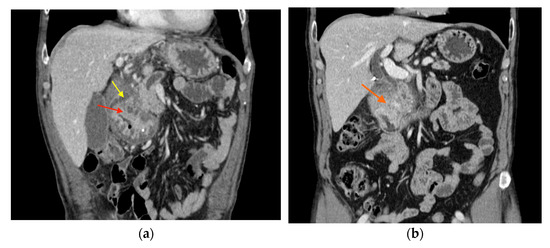

3.4. Imaging Findings

3.5. Pancreatic EUS